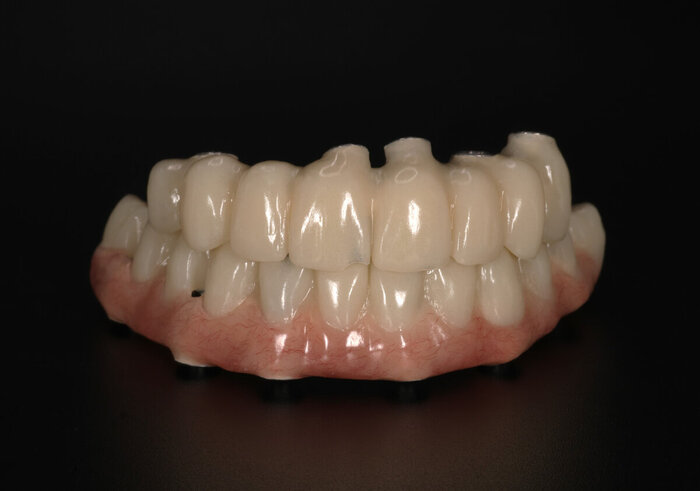

Временный адаптационный протез с опорой на 6 имплантов.

Временный адаптационный протез с опорой на 6 имплантов

Временный адаптационный протез с опорой на 6 имплантов. Нижняя челюсть.